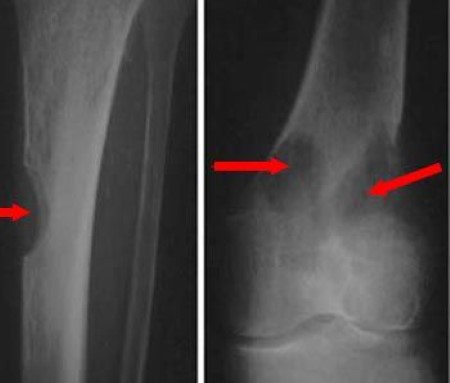

Pathological fractures bone fracture without a trauma history Bone pain. Some symptoms of progressing multiple. In some multiple myeloma patients the initial symptoms may be mild or easy to.

Multiple myeloma can also affect your bones leading to bone pain thinning bones and broken. Unfortunately these symptoms could mean any.

It is the most common type of cancer in men. Multiple myeloma causes many symptoms but bone pain often is the first symptom people notice. Myeloma cells inhibit your bodys ability to fight infections.